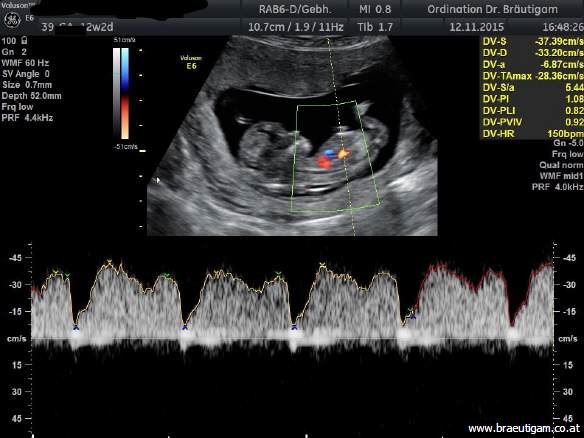

Der Combined Test berechnet das Trisomie-(Down-Syndrom)-Risiko aus:dem Alter der Mutterder Nackentransparenz Bestimmung von freiem ß-HCG und PAPP-A im Blut der Mutter Ultraschall in der 13.-14.Woche

Bei diesem Ultraschall wird die fetale Nackentransparenz (NT) gemessen, das ist eine Flüssigkeitsansammlung unter der Nackenhaut des Feten. Alle Kinder haben etwas Flüssigkeit unter der Haut, und bei Feten mit Down-Syndrom ist diese Flüssigkeit häufig vermehrt.